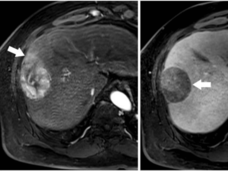

A large nationwide clinical trial called TMIST has been launched to compare two techniques used for mammograms: tomosynthesis, often called 3D mammography, and standard 2D digital mammography.